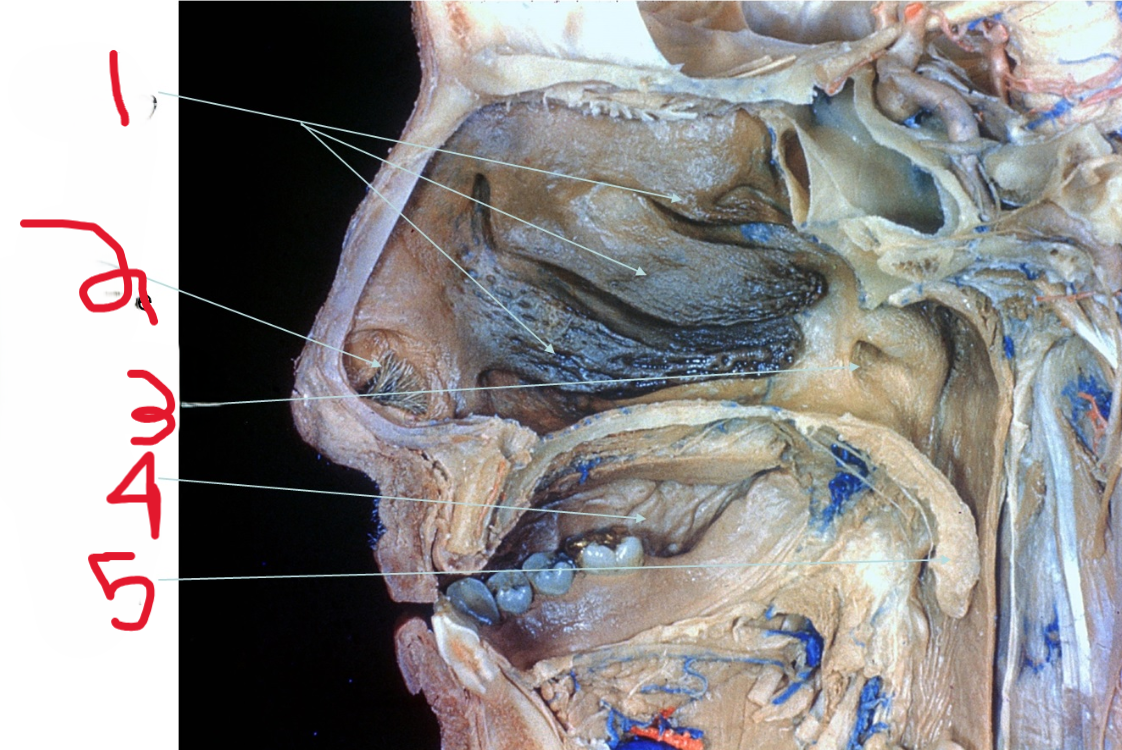

Nasal Conchae

What is depicted by #1

Nasal vestibule

What is depicted by #2

Opening of Pharyngotympanic (auditory) tube

What is depicted by #3

Oral cavity

What is depicted by #4

Uvala

What is depicted by #5